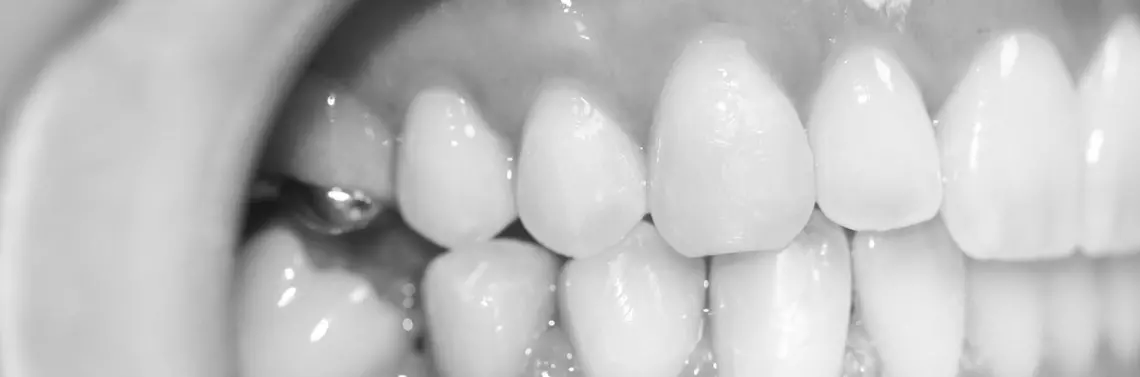

Opis przypadku – przebieg procedury (zdj. 8–14)

Pacjent zgłosił się do gabinetu ortodontycznego celem leczenia wady zgryzu. Po założeniu aparatu stałego wykonano zabieg zmniejszenia dolegliwości bólowych zgodnie z zaleceniami Farias i wsp. Końcówkę biostymulacyjną lasera diodowego o średnicy 8 mm przyłożono z lekkim uciskiem do dziąsła i wykonano naświetlanie brodawek międzyzębowych i okolic wierzchołków korzeni zębów żuchwy.

Zalecane ustawienia lasera:

• długość fali: 635 nm lub 808 nm,

• moc: 200 mW,

• tryb pracy: ciągła,

• czas naświetlania: 5 s,

• fluencja: 2 J/cm2,

• średnica końcówki: 8 mm.